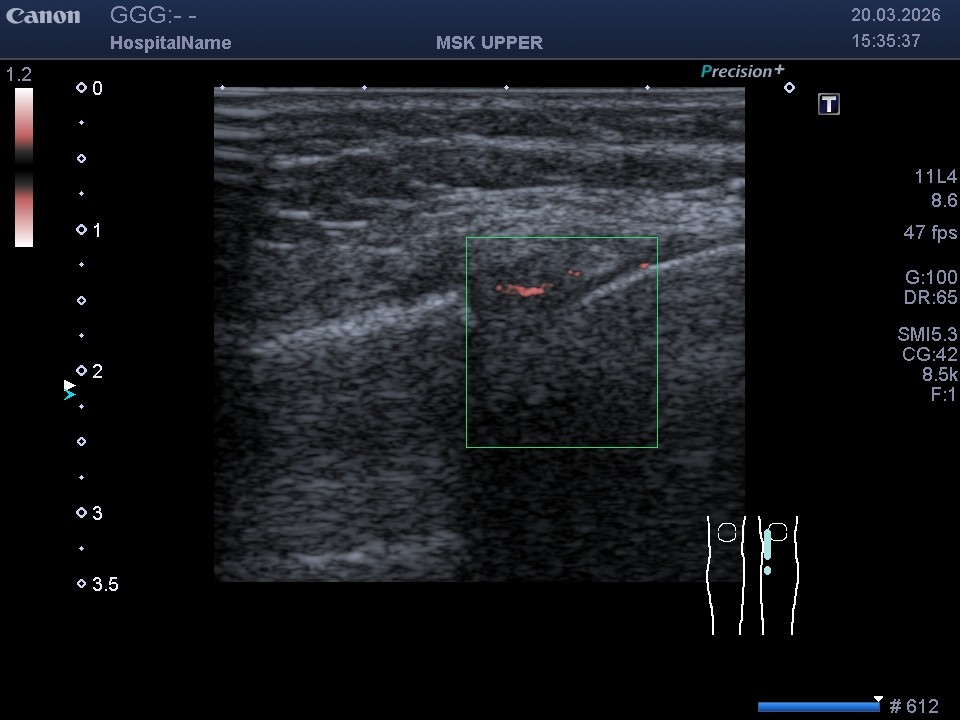

- Режим SMI (визуализация микроциркуляторного русла): С его помощью мы определяем кровоснабжение в «красной зоне» мениска, а также фиксируем появление неоангиогенеза в «белой зоне» после разрыва.

На обычном УЗИ отличить эти зоны невозможно. Однако включение режима SMI позволяет разграничить их по наличию доплеровского сигнала от микроциркуляторного русла. Иногда сосуды из красной зоны начинают мигрировать внутрь разрыва — это признак восстановления, который мы можем зафиксировать и отследить в процессе лечения.